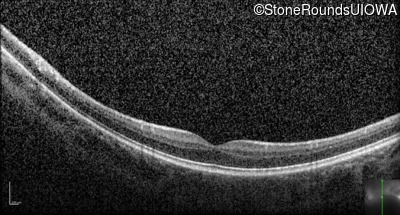

Optical Coherence Tomography - Right - 20/63 -2 sc

Exemplar / OCT Stack

OCT Stack